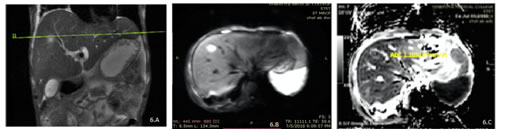

6

Figure 6-A, B, C: – A case of cholangitic abscess showing hyperintense lesion in the right lobe of liver on coronal T2eSSFSE sequence (A)with areas of diffusion restriction on DWI sequence (B) and corresponding areas of ADC reversal (C).